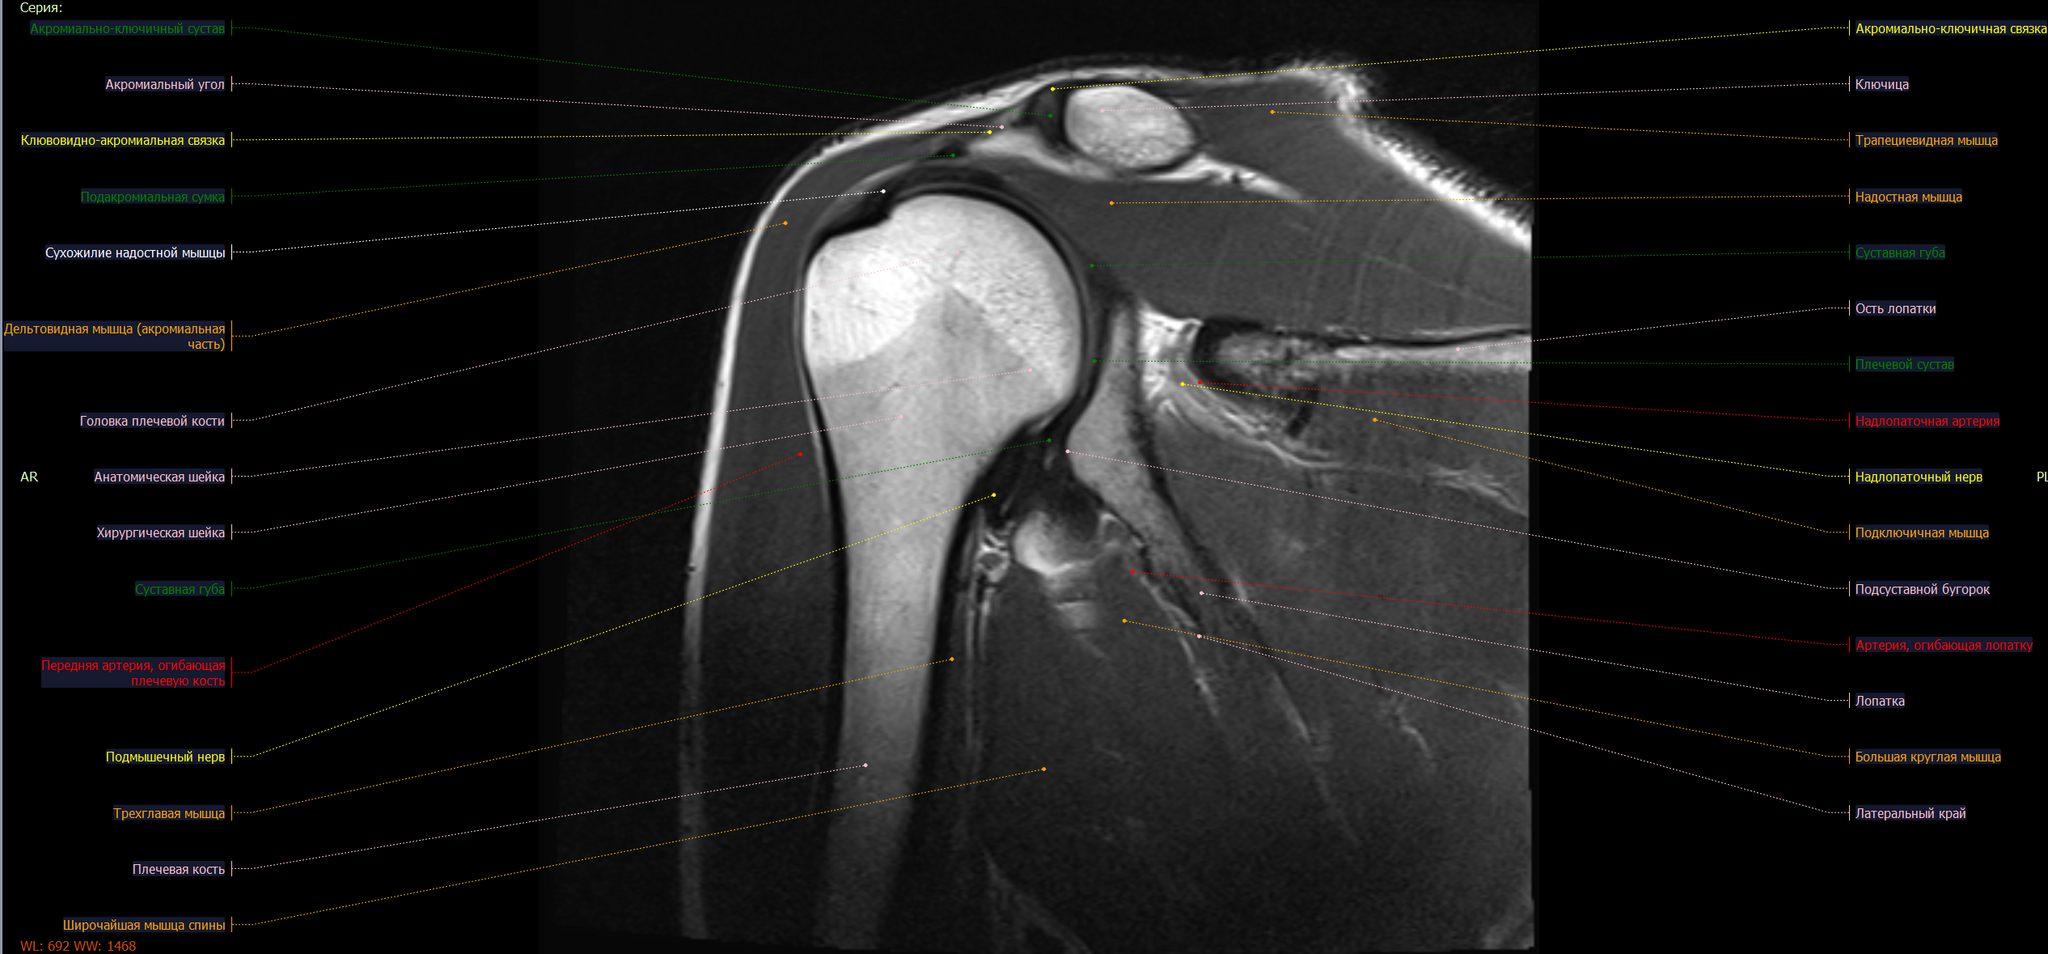

Импинджмент-синдром плечевого сустава – это состояние, при котором происходит сдавливание сухожилий мышц вращательной манжеты и субакромиальной сумки между головкой плечевой кости и акромиальным отростком лопатки.

Сужение субакромиального пространства до 5.4мм(норма 7мм),отек суставной поверхности акромиона, в полости субакромиальной сумки- умеренное количество выпота. Заключение: Субакромиальный импиджмент, субакромиальный бурсит правого плечевого сустава.